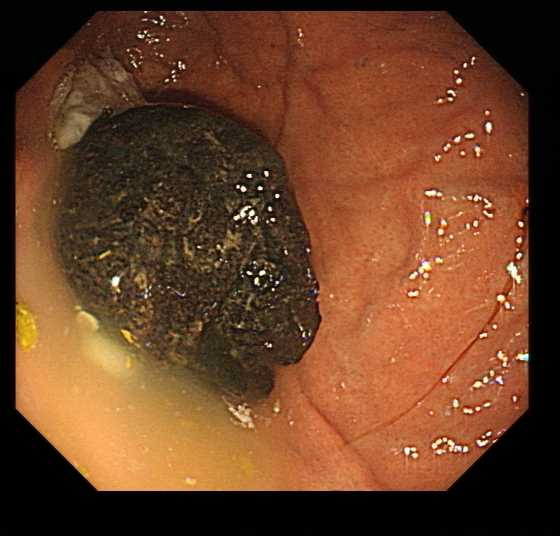

消化内科章辉医生听完金大妈的描述,安排了胃镜检查。当胃镜深入金大妈的胃部时,章医生惊讶地发现一个直径约5厘米的结石,通体乌黑,表面光滑,在胃镜灯光下闪烁着奇异的光芒,宛如修真小说中描述的“金丹”,而且由于结石反复摩擦胃壁,已经引起了多个胃溃疡,随时可能出现消化道出血风险。

“这种情况我们称为胃结石,也叫胃石症,”章医生向金大妈和她的家人解释,“某些食物在胃酸作用下会形成团块状异物,柿子中的鞣酸是常见原因之一。”